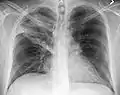

Normal AP CXR

Normal lateral CXR